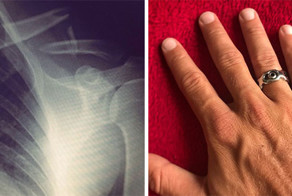

Южноафриканский мужчина, который надел обручальное кольцо на свой пенис "из соображений сугубо эротических", был госпитализирован в тяжелом состоянии на операцию.

28-летний уроженец Лимпопо, что к северу от Йоханнесбурга (ЮАР), был доставлен в больницу своей матерью в "состоянии нетерпимо сильной боли" после того, как его пенис... посинел.

Кольцо было так плотно прижато к разбухшей плоти, что врачи не смогли разрезать его с помощью острейшей хирургической пилы. Вместо этого, как только бьющегося в истерике пациента удалось усыпить, хирурги были вынуждены проколоть его орган и сделать кровопускание.

"Множественные проколы были сделаны с применением 20-ти мл шприца и 40 мм иглы. Как только отек спал, кольцо было успешно удалено", — сообщает журнал.

Мужчину из провинции Лимпопо лечили антибиотиками, давая обезболивающее, и через 3 дня он уже был выписан домой.